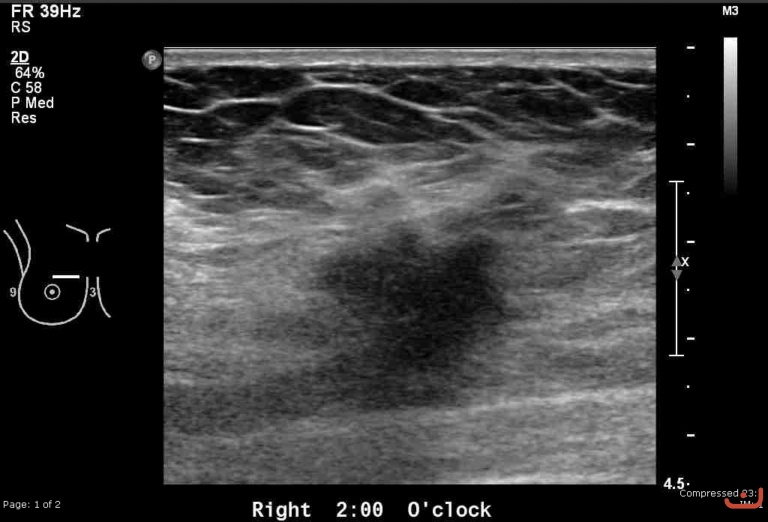

Malignant solid mass

Thursday, 30 April 2015

172.19 KB (768 x 522 px)